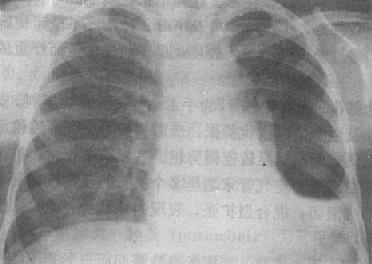

气胸的X线表现是由于胸腔内气体将肺压缩,使被压缩肺与胸壁间出现透明的含气区,其中不见肺纹理(图3-1-16)。肺被压缩的程度与胸腔内气体多少成正比。气体首先自外围将肺向肺门方向压缩,被压缩肺的边缘,呈纤细的线状致密影,呼吸时清楚。大量气胸可将肺完全压缩,肺门区出现密度均匀的软组织影。纵隔可向健侧移位,患侧膈下降,肋间隙增宽。张力性气胸时,可发生纵隔疝。健侧肺可有代偿性肺气肿。发生胸膜粘连,可见条状粘连带影。多处粘连,可将气胸分隔为多房局限性气胸。

右侧气胸伴右下胸膜粘连

图3-1-16 右侧气胸伴右下胸膜粘连

右肺萎陷,向肺门收缩,密度高,压缩肺与胸壁间

透明,其中未见肺纹理,肺底有粘连带与膈相连